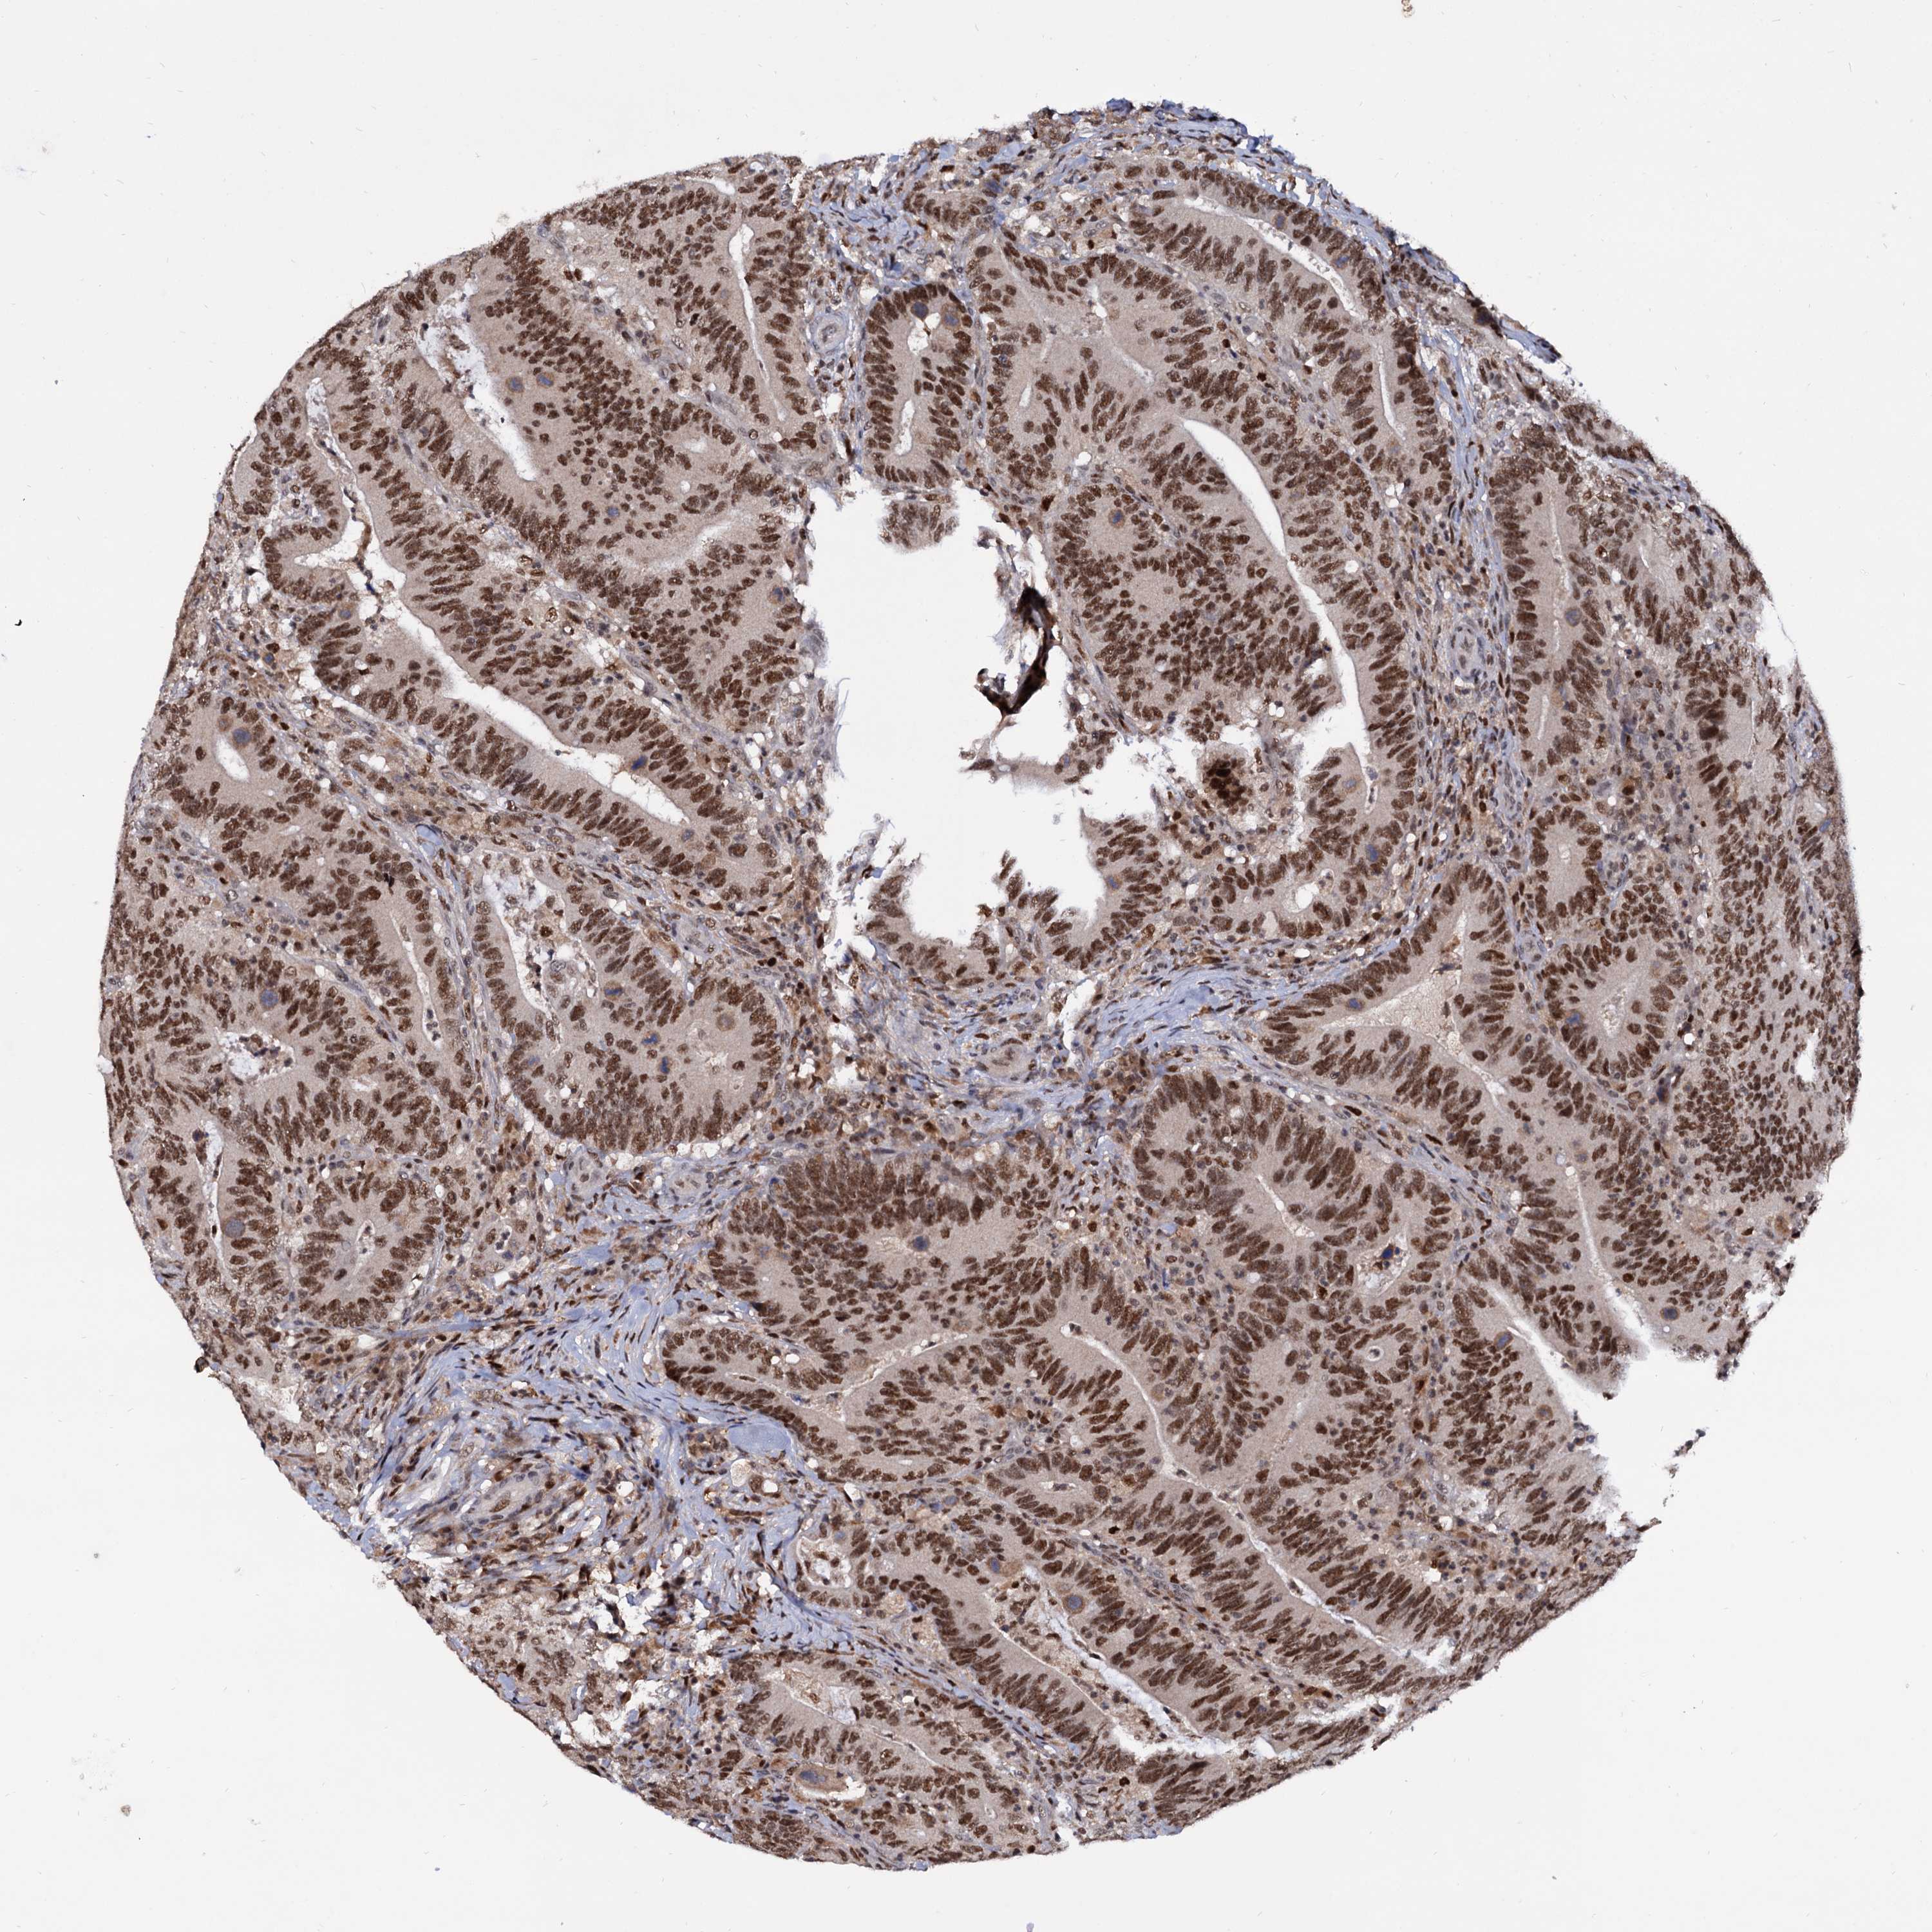

CANCER COLORECTAL CANCER Show tissue menu

Colorectal cancer

Colon adenocarcinoma